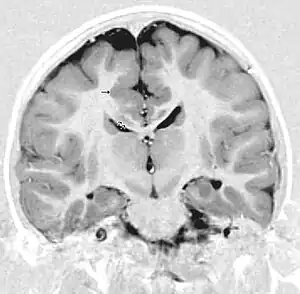

This child presented with seizures. The coronal true inversion recovery sequence shows thickened and disordered cortex in superior frontal and cingulate gyri bilaterally (arrow). There are small convolutions visible at the corticomedullary junction. The appearance is that of cortical dysplasia, with polymicrogyria more likely than pachygyria due to the small convolutions visible. There are also small foci of grey matter signal in the corpus callosum, deep to the dysplastic cortex (double arrows). These probably represent areas of grey matter heterotopia.